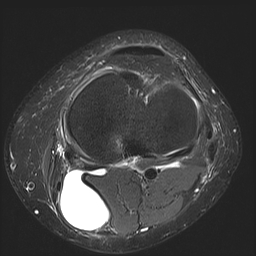

Worum handelt es sich bei dieser zystischen Struktur in der Kniekehle?